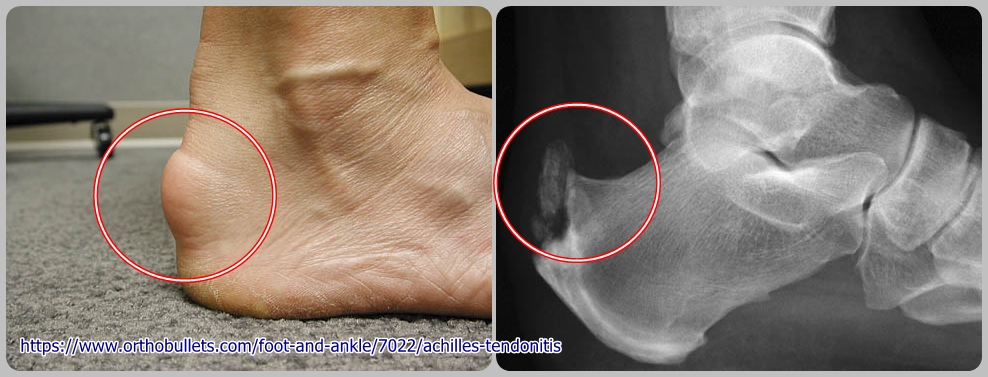

กลุ่มอาการปวดส้นเท้า เอ็นร้อยหวายอักเสบ ถุงน้ำเอ็นร้อยหวายอักเสบ กระดูกส้นเท้างอก(Haglund's heel) ![]() กลุ่มอาการปวดบริเวณส้นเท้า ดัดแปลงจากเอกสารของ ราชวิทยาลัยแพทย์ออร์โธปิดิกส์แห่งประเทศไทย กลุ่มอาการปวดบริเวณส้นเท้า ประกอบด้วย โรคหลาย ๆ โรค ที่ทำให้เกิดลักษณะอาการที่คล้ายคลึงกัน เช่น เอ็นร้อยหวายอักเสบ ถุงน้ำกระดูกส้นเท้าอักเสบ หรือ ถุงน้ำเส้นเอ็นร้อยหวายอักเสบ กระดูกเท้าบิดผิดรูป โรครูมาตอยด์ โรคเก๊าท์ กระดูกหัก เป็นต้น ซึ่งในบางครั้งอาจพบหลายโรคพร้อม ๆ กันก็ได้ อาการและอาการแสดง - มีอาการเจ็บบริเวณด้านหลังของส้นเท้า หรือ ด้านหลังข้อเท้า ซึ่งจะมีอาการมากขึ้นเมื่อมีการเคลื่อนไหวข้อเท้า เช่น เดินขึ้นลงบันได หรือ วิ่ง เป็นต้น - บางรายพบว่าการกดทับจาก ขอบด้านหลังของรองเท้า เวลาใส่รองเท้าทำให้เกิดอาการมากขึ้น ในผู้ที่เป็นมานาน บริเวณส้นเท้าอาจบวมหรือเป็นก้อนโตขึ้นได้ - ตำแหน่งที่เจ็บอาจจะอยู่ที่ เส้นเอ็นร้อยหวาย หรือ ด้านหลังต่อเส้นเอ็นร้อยหวายก็ได้ เมื่อกระดกข้อเท้าขึ้น จะมีอาการเจ็บมากขึ้น แต่เมื่อเหยียดข้อเท้าลง อาการก็จะดีขึ้น อาจคลำก้อนถุงน้ำ หรือ กระดูกงอกได้ การถ่ายภาพรังสี ด้านข้างของกระดูกข้อเท้าและส้นเท้า มักจะปกติ อาจพบมีกระดูกงอกได้ในผู้ป่วยบางราย ซึ่งในคนปกติ ที่ไม่มีอาการปวดส้นเท้า ก็อาจพบกระดูกงอกได้ ดังนั้นจึงไม่จำเป็นต้องถ่ายภาพรังสีในผู้ป่วยทุกคน แนวทางการรักษา การรักษาโดย ไม่ผ่าตัด ส่วนใหญ่แล้วการรักษาโดย ไม่ผ่าตัด จะได้ผลดี ซึ่งประกอบด้วย 1. ลดกิจกรรมที่ทำให้ปวด หรือ กิจกรรมที่ต้องลงน้ำหนัก เช่น การยืนหรือเดินนาน ๆ เป็นต้น และ ควรออกกำลังชนิดที่ไม่ต้องมีการลงน้ำหนัก เช่น ว่ายน้ำ ขี่จักรยาน 2. บริหารเพื่อยืดกล้ามเนื้อน่อง และ เส้นเอ็นร้อยหวาย 3. ใช้ผ้าพันที่ข้อเท้า ใส่เฝือกชั่วคราวในตอนกลางคืน หรือใส่เฝือกตลอดเวลา เพื่อลดการเคลื่อนไหวของข้อเท้า 4. ใส่รองเท้าที่เหมาะสม เช่น ขนาดกระชับพอดีไม่หลวมเกินไป ส้นสูงประมาณ 1–1.5 นิ้ว มีขอบด้านหลังที่นุ่ม หรือใช้แผ่นรองส้นเท้ารูปตัวยู ( U ) ติดที่บริเวณขอบรองเท้าด้านหลัง เพื่อไม่ให้ขอบของรองเท้ามากดบริเวณที่เจ็บ 5. หลีกเลี่ยงการเดินด้วยเท้าเปล่า 6. รับประทานยาแก้ปวด เช่น พาราเซ็ตตามอล ยาแก้ปวดลดการอักเสบ ประคบด้วยความร้อน หรือใช้ยานวด 7. ฉีดยาสเตียรอยด์ บริเวณที่มีการอักเสบ ทุก 1-2 อาทิตย์ แต่ ไม่ควรฉีดเกิน 2 ครั้งใน 1 เดือน ถ้าไม่จำเป็นก็ ไม่ควรฉีด เพราะอาจเกิดผลแทรกซ้อนได้ เช่น เส้นเอ็นร้อยหวายขาด ผิวหนังบริเวณที่ฉีดเปลี่ยนเป็นสีขาว เป็นต้น การรักษาโดยการผ่าตัด ข้อบ่งชี้ในการผ่าตัด 1. ผู้ป่วยที่ตอบสนองต่อการรักษาดี แต่กลับเป็นซ้ำบ่อย ๆ ไม่หายขาดทำให้มีปัญหาในการดำเนินชีวิตประจำวัน 2. ในรายที่ตอบสนองต่อการรักษาไม่ดี โดยเฉพาะรายที่มีสาเหตุชัดเจน เช่น ฝ่าเท้าบิดเข้าหรือบิดออก เป็นต้น วิธีผ่าตัด เช่น ผ่าตัดเพื่อเอาถุงน้ำ เนื้อเยื่อที่อักเสบ และ กระดูกงอก ออก หรือ ผ่าตัดเปลี่ยนแนวกระดูก เป็นต้น ผลข้างเคียงที่อาจพบได้ เช่น แผลเป็นนูนทำให้ปวดแผลเรื้อรัง เส้นเอ็นร้อยหวายขาด เป็นต้น ![]() """""""""""""""""""""""""""" ![]() ข้อสังเกต เกี่ยวกับ การฉีดยาสเตียรอยด์เฉพาะที่ - เส้นเอ็นฝ่าเท้าอักเสบ (กรอบสีเขียว) .. แนะนำให้ฉีด เพื่อบรรเทาอาการปวด - เส้นเอ็นร้อยหวายอักเสบ (กรอบสีแดง) .. " ไม่แนะนำ " ให้ฉีด (เนื่องจากอาจทำให้เกิดเส้นเอ็นร้อยหวายขาดได้) Heel Pain: Diagnosis and Management https://www.aafp.org/pubs/afp/issues/2018/0115/p86.html Diagnosing Heel Pain in Adults https://www.aafp.org/pubs/afp/issues/2004/0715/p332.html Heel pain: a practical approach https://www.racgp.org.au/afp/2015/march/heel-pain-a-practical-approach Plantar Heel Pain https://www.physio-pedia.com/Plantar_Heel_Pain Plantar Fasciitis | Plantar Fasciopathy | Diagnosis & Treatment https://www.physiotutors.com/conditions/plantar-fasciitis/ Heel Pain in Runners – More than Just Plantar Fasciitis! https://www.physiotutors.com/heel-pain-in-runners/ Tools to speed your heel pain diagnosis https://ma1.mdedge.com/content/tools-speed-your-heel-pain-diagnosis ....................................... ![]() ![]() Summary Achilles Tendonitis consists of a series of 3 conditions affecting the achilles tendon which include: insertional Achilles tendonitis, retrocalcaneal bursitis & Haglund deformity, and Achilles tendonitis. Retrocalcaneal bursitis is inflammation of the bursa between the anterior aspect of the Achilles and posterior aspect of the calcaneus Haglund deformity an enlargement of the posterosuperior tuberosity of the calcaneus Treatment nonoperative activity modification NSAIDs shoe wear modification external padding of Achilles tendon heel lifts heel sleeves and pads (heel cushion) (modified shoes with silicon) cast or removable boot (locked ankle AFO) for 6-9 months (if other nonoperative modalities fail) physical therapy with eccentric training gastrocnemius-soleus stretching Extracorporeal shock wave therapy, Laser treatment therapy PRP injections avoid steroid injections due to risk of Achilles tendon rupture operative retrocalcaneal bursa excision, Achilles debridement and resection of Haglund deformity ( calcaneal bony prominence resection ) """""""""""""""""""""""""""""""" เอ็นร้อยหวายอักเสบ ปวดเอ็นร้อยหวาย เสี่ยงอักเสบและฉีกขาด! https://kdmshospital.com/article/achilles-tendinitis/ Calcaneal spure (ภาวะกระดูกอ่อนงอกที่ส้นเท้า) https://pt.mahidol.ac.th/ptcenter/knowledge-article/calcaneal_spure/ https://www.orthobullets.com/foot-and-ankle/7022/achilles-tendonitis https://my.clevelandclinic.org/health/diseases/25134-haglunds-deformity https://www.physio-pedia.com/Haglund%27s_deformity https://www.medicalnewstoday.com/articles/322432#exercises https://www.eorthopod.com/content/haglunds-deformity ........................................... กลุ่มอาการปวดส้นเท้า เอ็นร้อยหวายอักเสบ ถุงน้ำเอ็นร้อยหวายอักเสบ กระดูกส้นเท้างอก(Haglund's heel) https://www.bloggang.com/viewblog.php?id=cmu2807&date=24-07-2008&group=5&gblog=34 เส้นเอ็นร้อยหวาย ขาด [ Achilles tendon ruptures ] https://www.bloggang.com/viewblog.php?id=cmu2807&date=21-06-2009&group=6&gblog=29 เส้นเอ็นฝ่าเท้าอักเสบ ( รองช้ำ ) https://www.bloggang.com/viewblog.php?id=cmu2807&date=23-07-2008&group=5&gblog=33 เป็นแบบนี้เหมือนกันเพราะ เรา นน.เยอะเกินไปหรือเปล่า